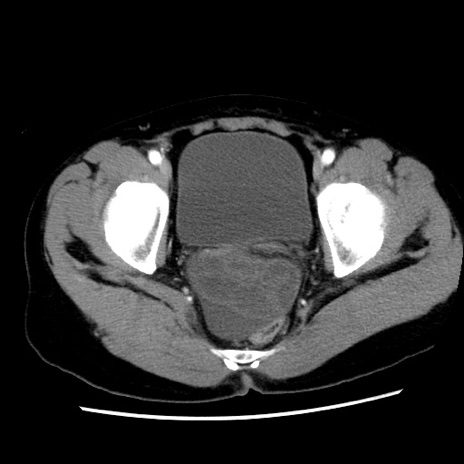

症例10(横断像)

【症例】 50歳代女性

【主訴】 腹痛

【現病歴】前日生レバーを食べた。今朝に排便あり。 昼前に突然発症の腹痛を生じ、当院救急外来を受診した。

【既往歴】 子宮筋腫にてで子宮全摘後

【身体所見】 意識清明、腹部:平坦、軟、下腹部やや左を中心に圧痛・反跳痛あり、筋性防御あり

【データ】WBC 7800、CRP 0.07